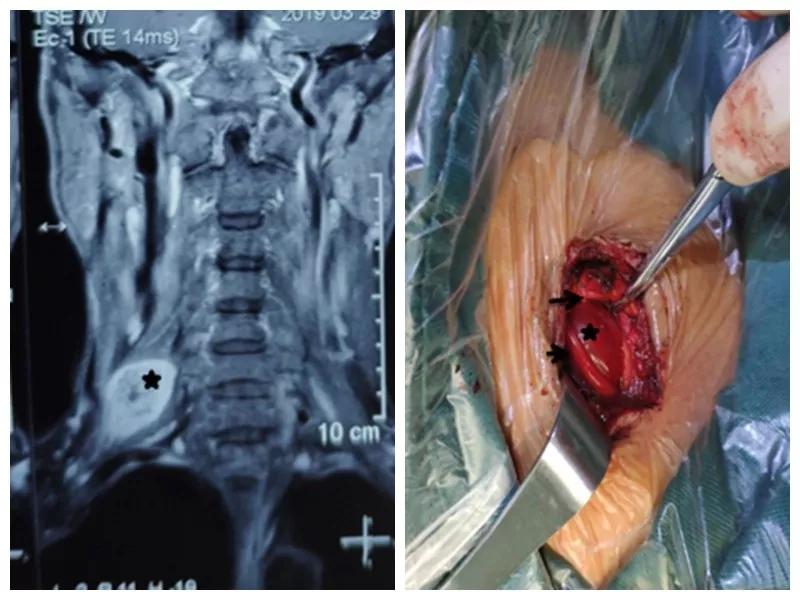

家住户县的王师傅一年前无意中发现右颈部长了一个“包”,当时并未在意,但是他发现这个“包”逐渐增大,并且伴有压痛,按压这个“包”时还可引起右胳膊疼痛,在当地医院就诊,未见好转,在我市某三甲医院检查及包块穿刺活检示右侧颈部神经鞘瘤,医生告诉他可以手术切除,但是风险很大。王师傅慕名来到西安市中心医院骨一科就诊,严少荣主任接诊后立即安排住院治疗,并安排由西安市手外科常委王涛主任医师及主治医师张磊组成治疗小组。积极进行术前检查,发现右颈部肿瘤有3×3×3 cm大小活动性差的肿瘤。并有触电样感觉向肢体放射。经过制定缜密手术方案,严主任细心耐心告知患者手术的风险性,并安排术中神经电生理监测,提高手术安全性,由王涛主任医师、张磊主治医师和麻醉医师李楠及手术护士组成手术团队,在全麻下行右侧颈部神经鞘瘤切除术,术中发现此神经鞘膜瘤巨大,位于臂丛神经上干并包饶颈5.6神经,与周围组织黏连严重,由于该肿瘤起源于神经根纤维许旺氏细胞,遂着肿瘤不断生长,将神经干内正常神经纤维挤向肿瘤四周,包含在神经外膜内形成肿瘤的“包膜”呈鱼肉样。王涛主任医师在仔细保护神经的情况下采用“层层剥离挤出法”将肿瘤取除,避免了误将含正常神经纤维的“包膜”随肿瘤一起切除,造成神经干损伤及缺失,从而造成上肢功能的不可逆障碍的悲剧。术后经过主管护士解妍及全体医护人员的精心治疗护理,王师傅原有神经压迫症状消失,无任何感觉运动异常,术后再次病检符合神经鞘瘤。王师傅满意出院。